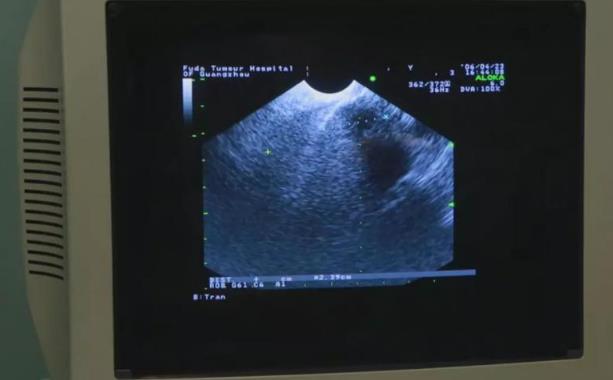

Alberto P.Mallari先生于2018年11月30日第一次到廣州復(fù)大腫瘤醫(yī)院住院。經(jīng)過專家們的檢查和評價,2018年12月5日Alberto先生接受了微創(chuàng)前列腺癌冷凍消融和碘-125粒子植入的聯(lián)合治療,治療過程非常順利,12月14日,Alberto先生高興地出院。

2019年2月,又到廣州復(fù)大腫瘤醫(yī)院在馬尼拉的辦事處提供免費腫瘤咨詢時,Alberto先生來了。看到2月11日馬尼拉UERMMRI 中心的MRI結(jié)果時,醫(yī)生真是心花怒放,只見報告寫道:Prostategland: Normal in size2.5x3.2ⅹ3.1cm(AP/T/CC)with a volume of 12.5cm3(previously 31cm3).The previously notedlesion involving the left anterior transitional zone and leftanterior stroma is no longer seen. PSA值0.25ng/ml.